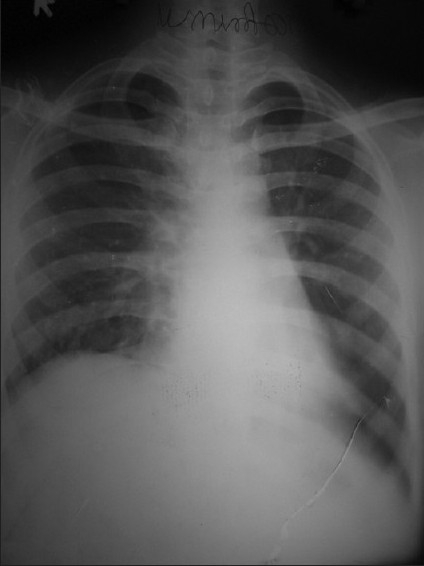

An 18-year-old male patient presented in September 2006 with dull retrosternal and right-sided chest pain, dyspnea and dysphagia for solids of 1-month duration. Chest X-ray showed lobulated homogenous opacity occupying the right mid-zone and lower zone [Figure 1]. There was no calcification.

| Figure 1 Chest X ray PA view (2006) shows homogenous opacity in right mid and lower zone